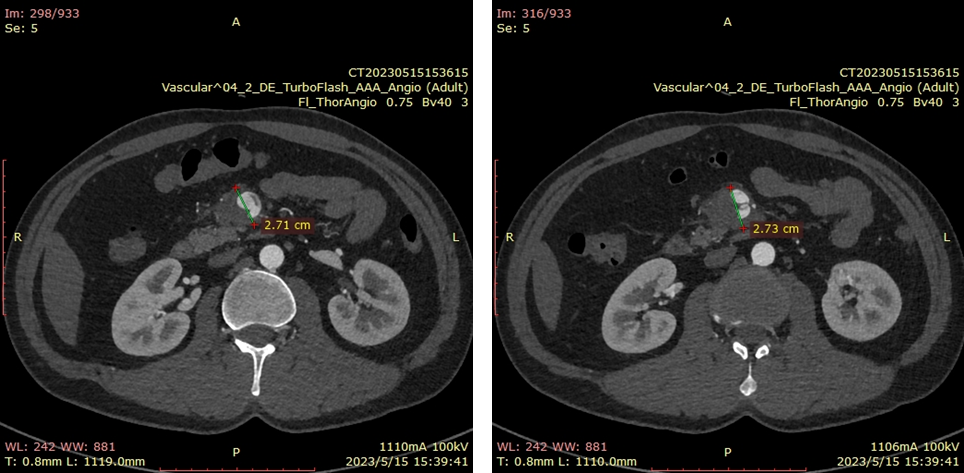

20230515CTA(保守治疗2周我院复查)